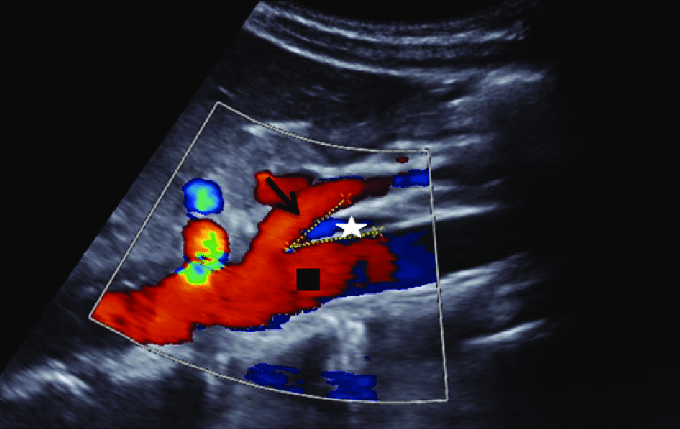

Se ha observado que los neonatos que desarrollan NEC tienden a tener una velocidad sistólica máxima y un índice de resistencia más altos en la SMA durante el primer día postnatal.[1] Además, el flujo diastólico en la SMA y el tronco celíaco normalmente debe ser anterógrado, y cualquier alteración en este flujo puede indicar problemas hemodinámicos significativos.[3-4]